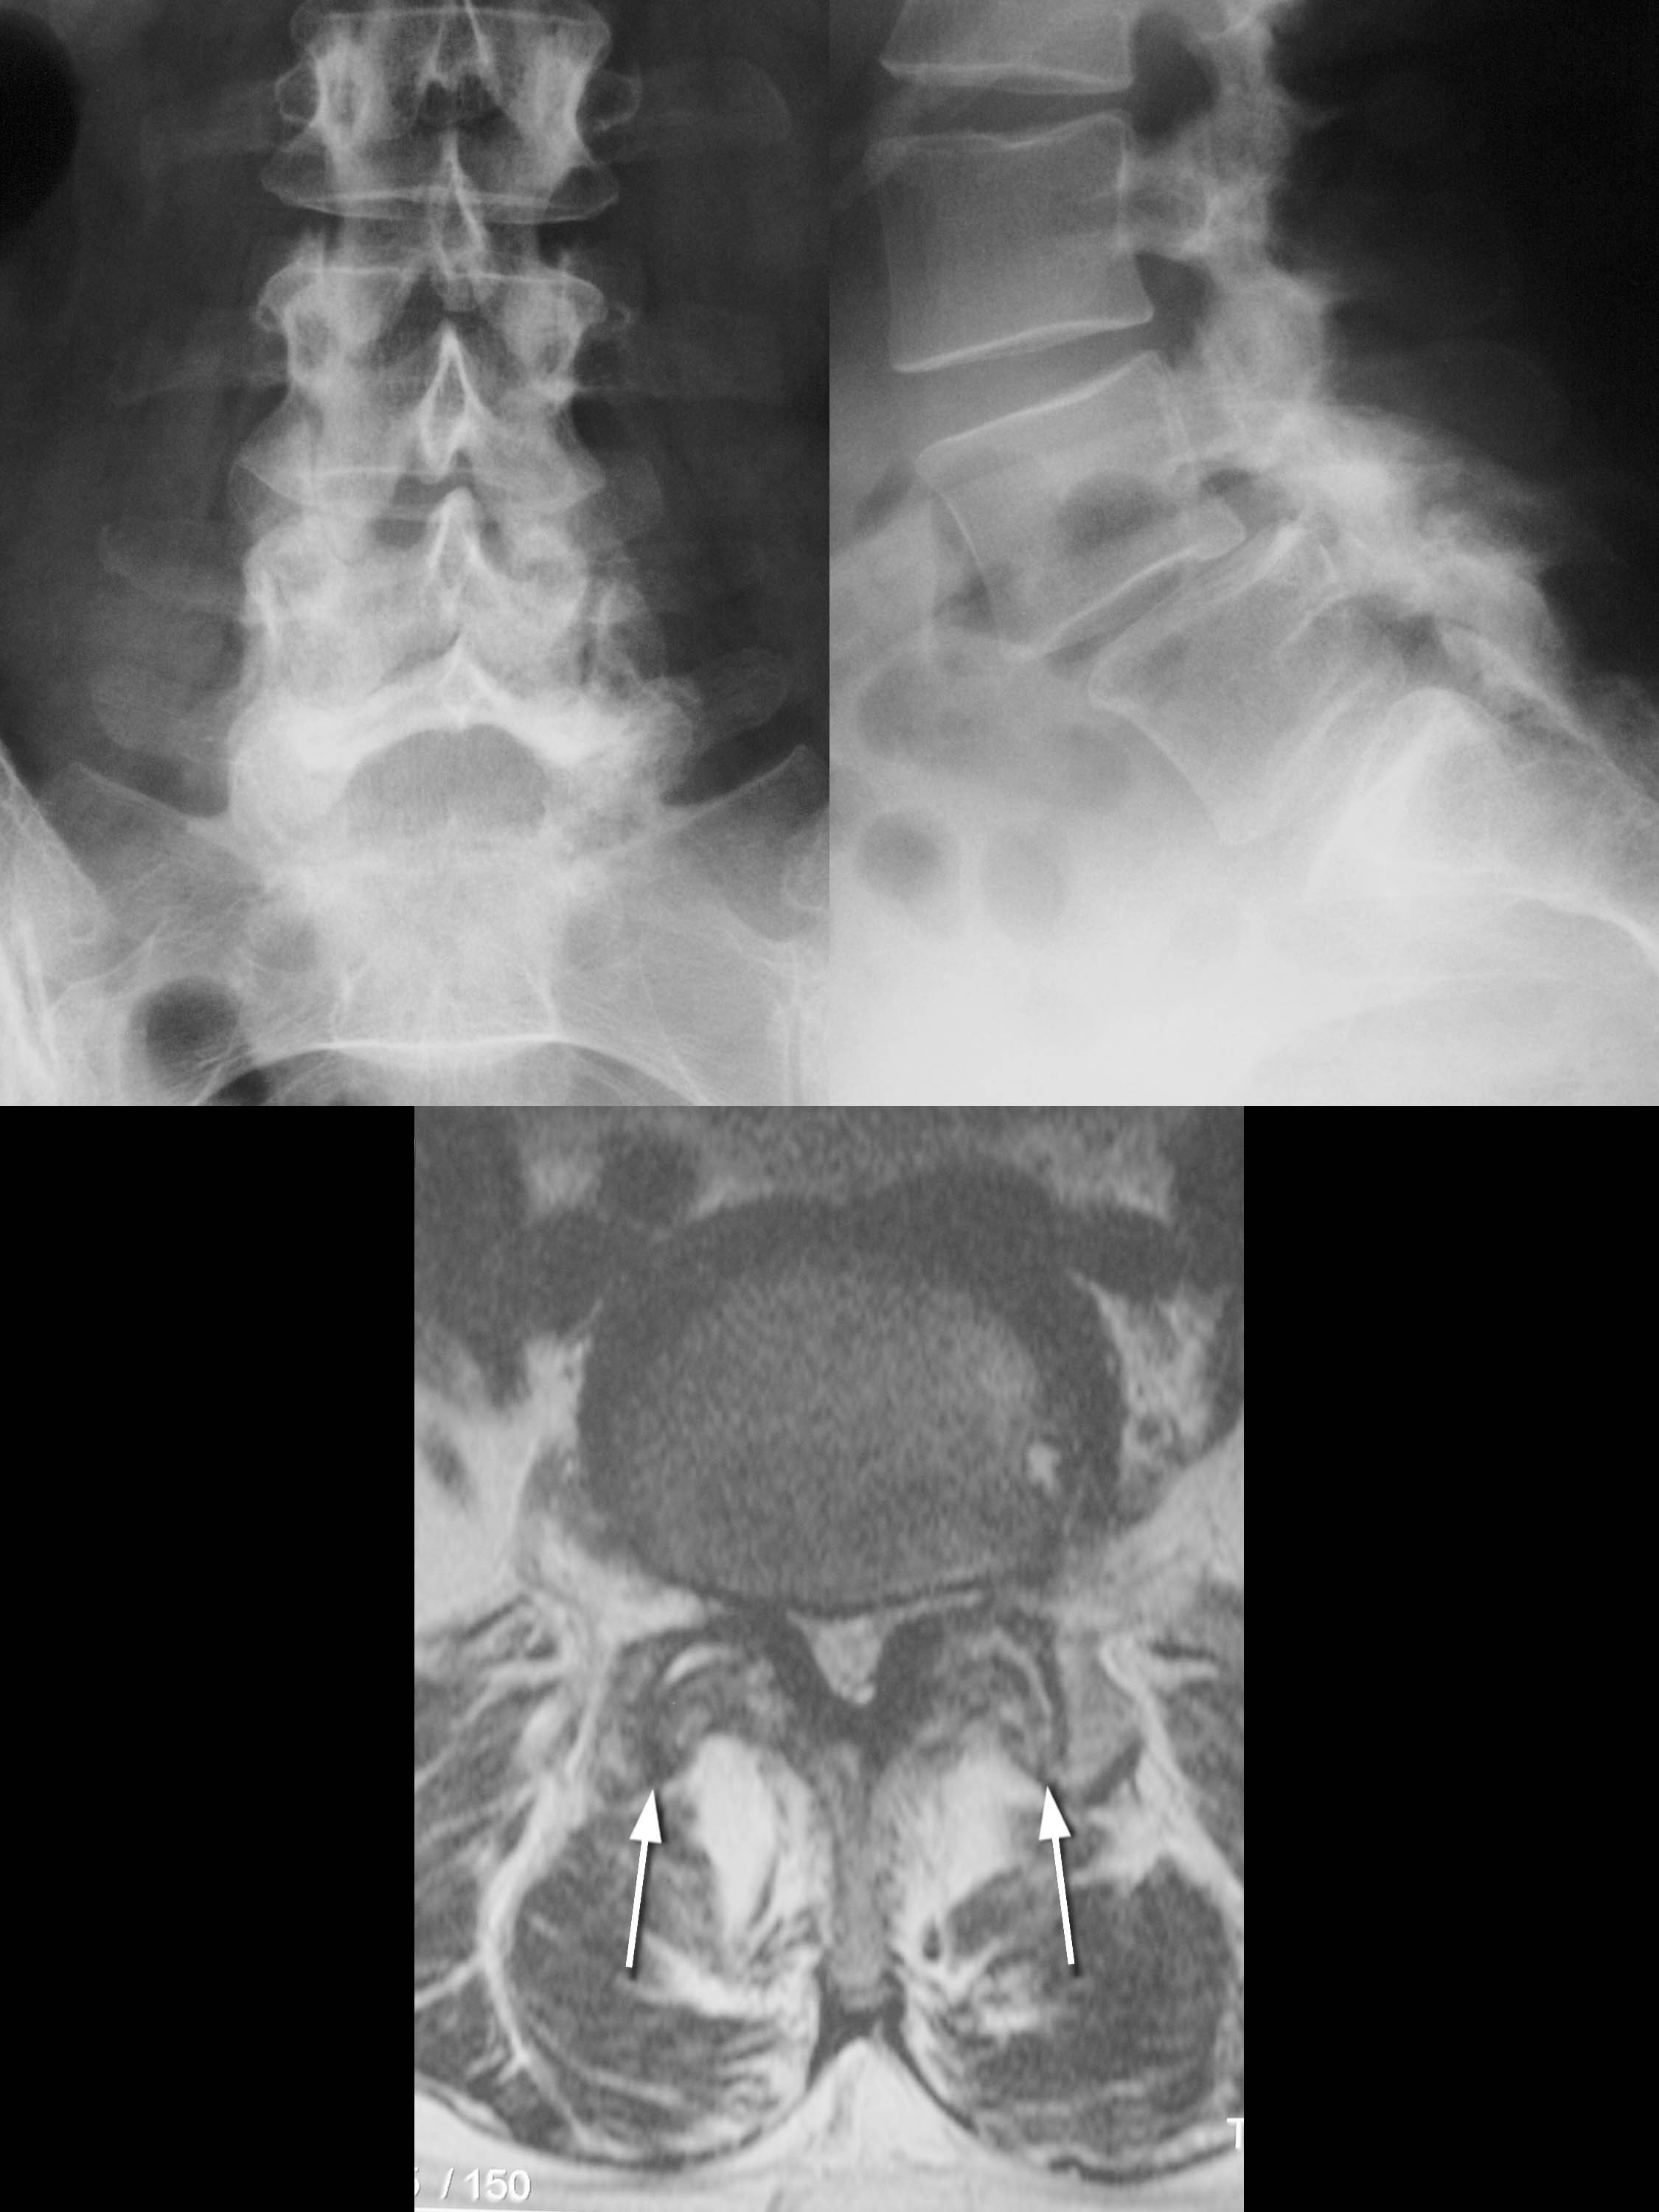

Sobre su fisiopatología se piensa que se produce por una isquemia sufrida por las raíces nerviosas lumbosacras secundaria a compresión por las estructuras que las rodean, (las facetas o carillas articulares hipertrofiadas, el ligamento amarillo, osteofitos vertebrales, tejido cicatricial o discos abombados, protruidos o francamente herniados.[1]